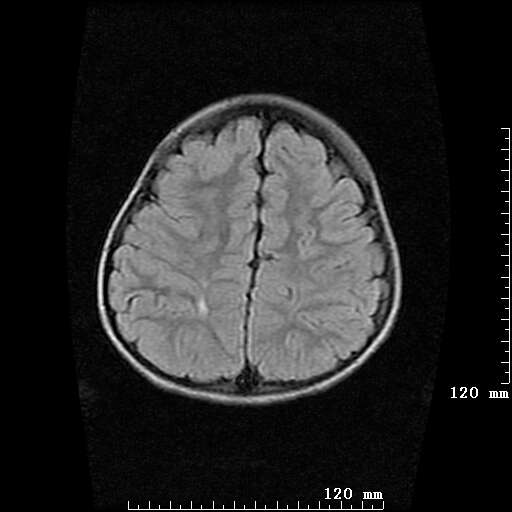

女,7岁,三岁才说话、走路。现智力尚可,走路不稳。临床怀疑大脑发育不全。

考虑 脑白质发育不良

脑折质变薄,双侧侧脑室稍扩张,支持考虑脑折质发育不良

侧脑室周围白质软化症。

考虑胼胝体发育不全,髓鞘形成不良。

支持考虑胼胝体发育不全,髓鞘形成不良。

脑裂畸形伴灰质异位

侧脑室周围白质数量减少,侧脑室不对称性扩大,左侧侧脑室后角呈方形改变,脑沟加深,结合临床考虑脑室周围白质软化症(pvl)。期待结果!

只看出灰质异位

支持脑白质发育不良。